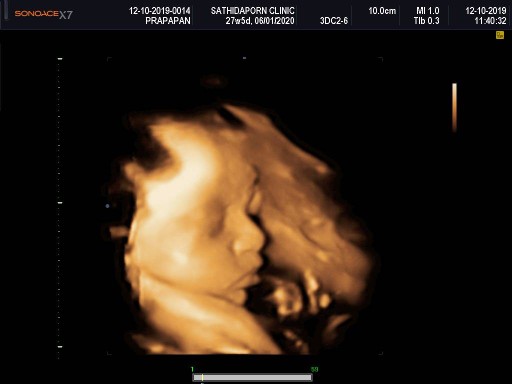

บ้านนี้ซาวตอน 28W จ้า